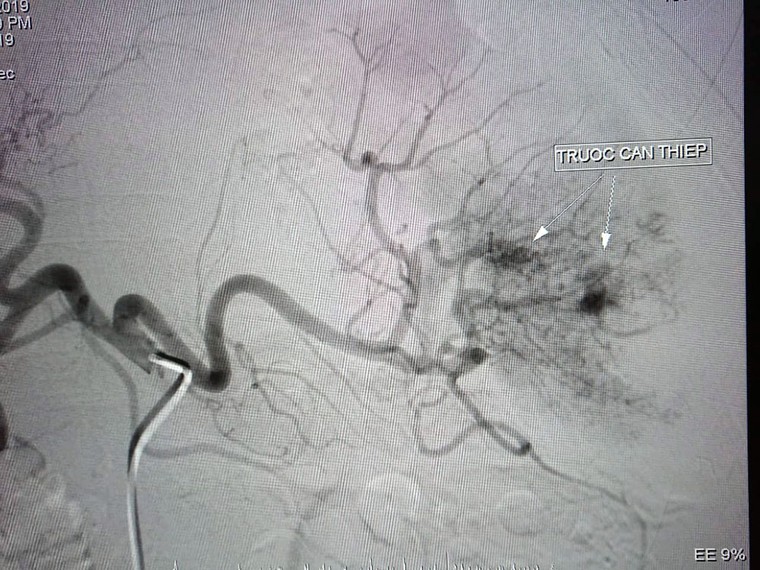

Kết quả phát hiện dò động mạch thận phân thuỳ dưới thận trái tạo thành giả phình động mạch thận trái.

Ê kíp can thiệp do BS CK1 Trần Công Khánh và Phạm Minh Phước đã tiến hành nút tắc bằng 1 coil.

Sau khi đặt coil, bác sĩ tiến hành chụp kiểm tra và cho kết quả đã bít hoàn toàn lỗ dò động tĩnh mạch và đoạn giả phình mạch.

Hình ảnh trước khi can thiệp giả phình mạch thận sau chấn thương cho bệnh nhân |